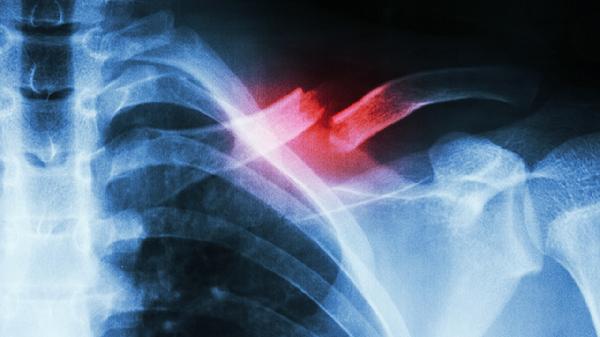

肋骨骨折多长时间不疼

肋骨骨折一般需要3-6周疼痛逐渐缓解,具体时间与骨折严重程度、个人体质及护理措施有关。

单纯性肋骨骨折未合并内脏损伤时,疼痛通常在1-2周内减轻,3-4周后明显缓解。此阶段需避免剧烈运动、咳嗽时用手按压患侧胸部,可遵医嘱使用布洛芬缓释胶囊、塞来昔布胶囊等药物镇痛。若骨折端稳定,胸带固定有助于减轻呼吸时肋骨移动带来的疼痛。部分患者因神经敏感或愈合较慢,可能需4-6周疼痛才会显著改善。高龄、营养不良或合并慢性疾病者恢复时间可能延长至6-8周。疼痛持续期间应保持半卧位休息,避免侧卧压迫患处,饮食需增加富含钙质的食物如牛奶、豆腐,促进骨痂形成。

若疼痛超过8周未缓解或伴随呼吸困难、发热,可能提示骨折移位、肺部感染等并发症,需及时复查胸部CT。开放性骨折、多发性骨折或合并血气胸者,疼痛周期可能延长至2-3个月,需通过手术复位固定或胸腔闭式引流治疗。吸烟患者应严格戒烟,避免延缓愈合。康复期可在医生指导下进行深呼吸训练,预防肺不张。